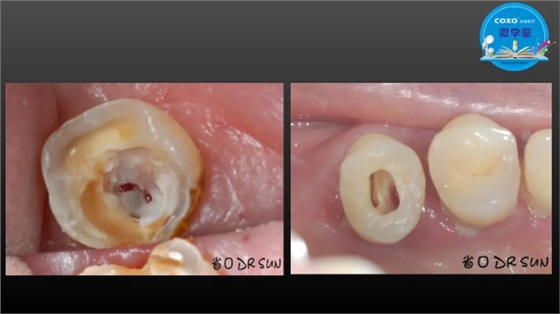

主任医师,牙体牙髓副主任, 广东省口腔医院牙体牙髓科 主任医师。2003年硕士研究生毕业,研究方向为牙体牙髓病学,擅长于牙体牙髓病的诊断、龋齿、牙髓炎、根尖周病的治疗以及前牙美容修复。